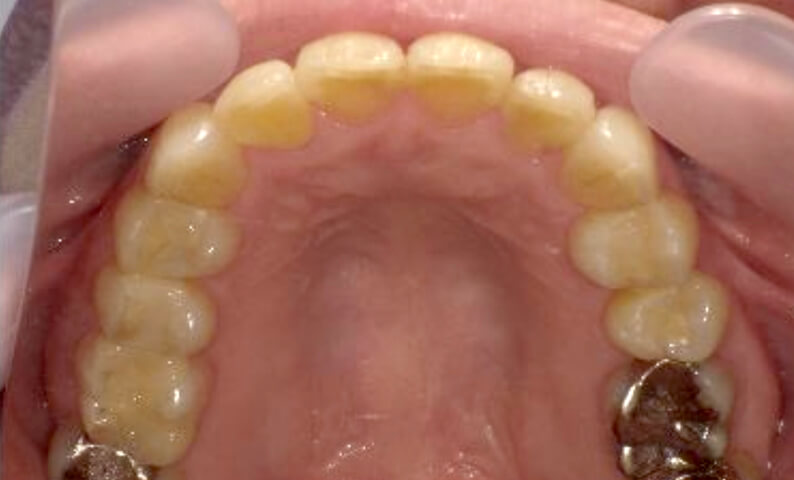

症例_002 上顎だけの部分矯正

治療期間:7ヶ月金額:30万円+税女性前歯のガタガタ上の前歯だけ

| Before | After |

|---|---|

|